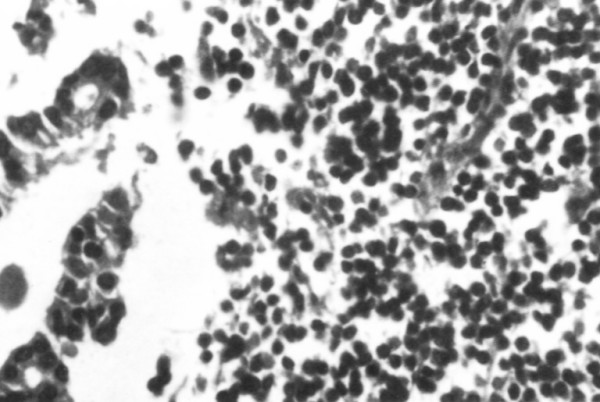

Subsequent  pathologic  examination of the removed lymph node showed total  infiltration from  a low  grade lymphoma; with a limited metastatic infiltration from  an adenocarcinoma noted in the same specimen (Figure 2).

2 fig 2